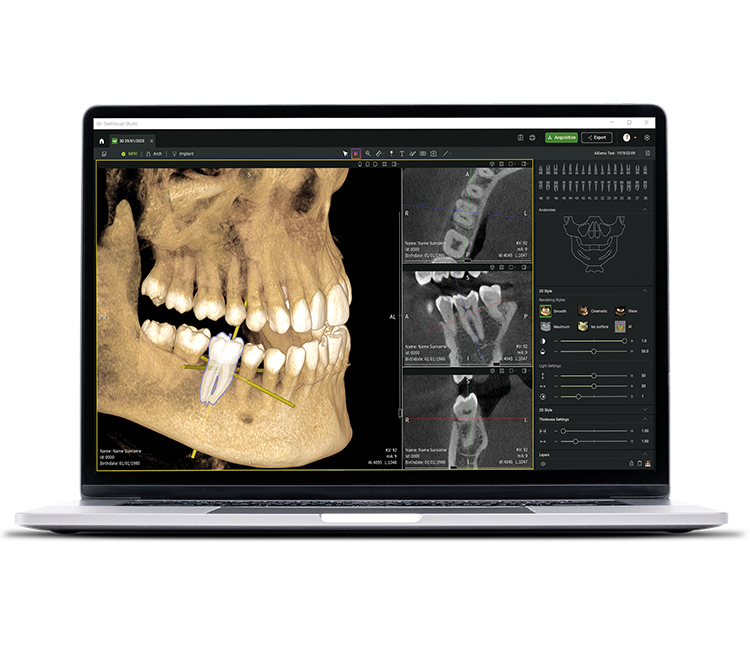

• Seethrough Studio

See tomorrow. See a new level.

Insieme alle tecnologie hardware di ultima generazione, Seethrough Studio rappresenta l'elemento rivoluzionario e differenziante del portfolio imaging W&H. Con funzioni avanzate e algoritmi intelligenti, Seethrough Studio offre un'esperienza all-in-one che spinge verso nuovi orizzonti la qualità dell'imaging e l'efficienza dei workflow digitali.

Sistema integrato di pianificazione dell'impianto

Oltre all'eccezionale qualità delle immagini e al funzionamento intuitivo, Seethrough Studio offre numerose funzioni utili, come la funzione integrata di pianificazione implantare: una soluzione semplice, precisa e facilmente consultabile.

IA - Intelligenza Artificiale

Seethrough Studio utilizza diversi strumenti di intelligenza artificiale per ottenere immagini ancora migliori, come l'allineamento dei volumi 3D, la segmentazione dei denti, la generazione di linee d'arcata e il riconoscimento automatico del nervo. Inoltre, offre un utile supporto per l'identificazione di patologie.